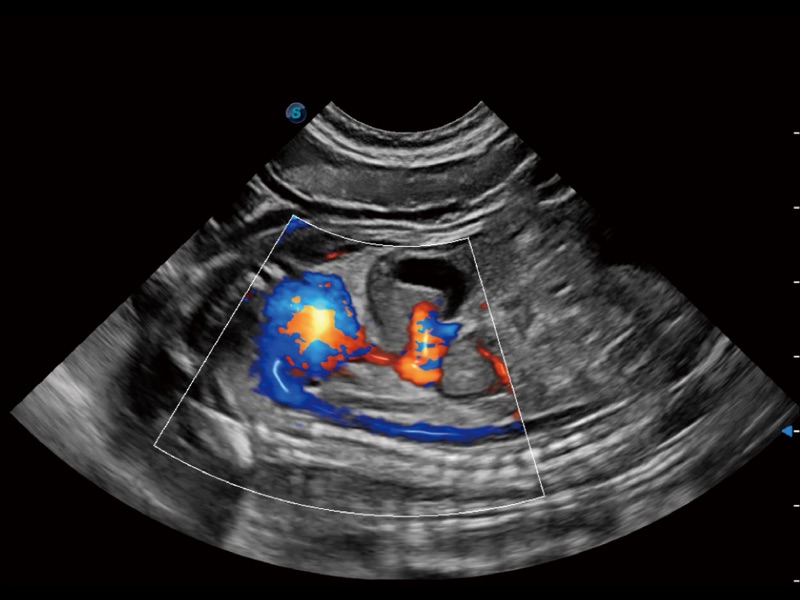

• Micro F 显微血流成像

通过创新的 Matrix E自适应滤波器和超长时间域算法,极大提升超低速微细血流的检出能力,同时更精准地滤除软组织和噪声信号,为兽用医生提供以往无法通过常规血流获得的疾病诊断信息。

• 宽景成像

通过色彩血流和实时宽景相结合,可观察到完整的静脉或动脉的血流,方便医生检查。实时扫查过程中,如有任何操作失误也可以很容易地进行回扫擦除,而不会中断扫查。

优异的基础图像

ProPet 70 全新的动物超声智能软件和丰富的探头群,为动物医生提供了高清晰度和精细分辨率的图像,无论在宠物、马科、畜牧还是实验室动物等应用中都可以轻松应对,为您的日常工作带来满意的体验。

(犬)左室长轴血流

(犬)髂动脉血流

(犬)胎儿主动脉弓立体血流